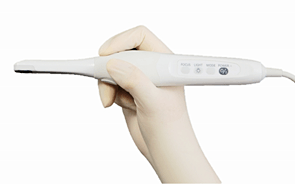

口腔内カメラです。

実際には自分の目で直接見ることができない口の中を、拡大してみることができます。